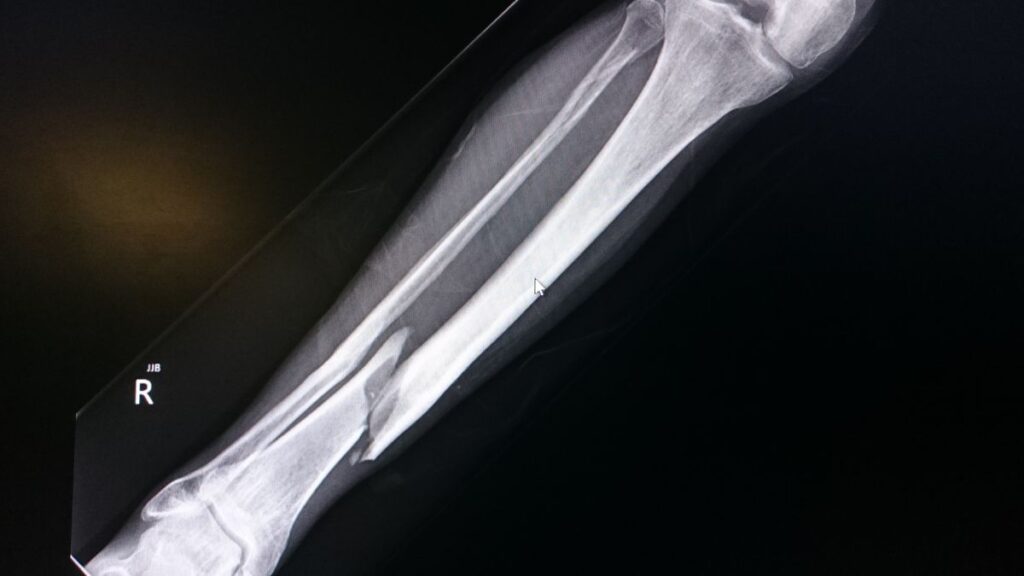

年齢とともに増える骨折リスクにしっかり備えられる

パンフレットでは、50代から90代に向けて骨折リスクが急増するグラフが掲載されています。

「生きる未来」では、骨折見舞金(最大1〜3万円)が用意されており、シニアに必要な保障を過不足なくカバーしています。